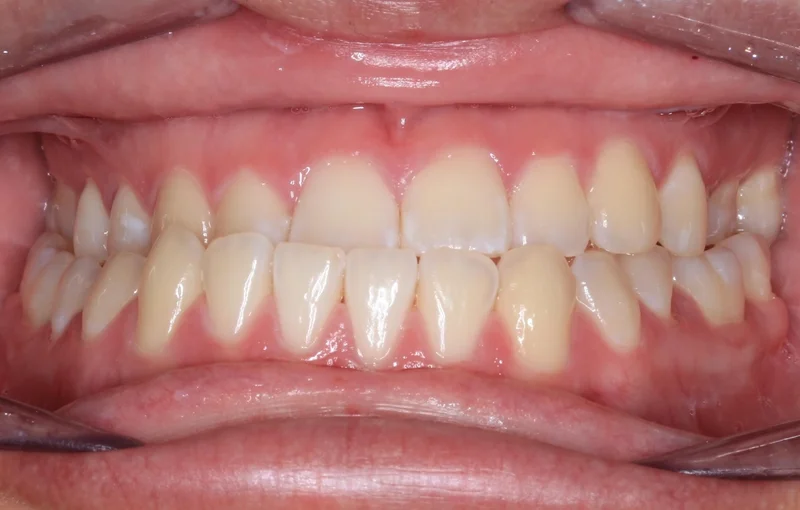

Case #90850 | 18 - 29 | Female

This young woman in Las Vegas came to us with a severe class III malocclusion (underbite) and the only option to correct her bite was with extractions on the upper arch and orthognathic surgery with an oral surgeon. She needed to have two teeth extracted first on the upper arch as part of the presurgical orthodontics to correct the severe proclination of the upper incisors. We first decompensated for this proclination by uprighting the upper incisors and closing the extraction space, which actually makes the overjet worse prior to surgery. She then had a double jaw surgery, including a Le Fort maxillary advancement as well as a mandibular setback. After about 6 weeks of post-surgical healing, she resumed orthodontic treatment to finish up. Her total treatment time was 27 months.

Center - Before Treatment

Before